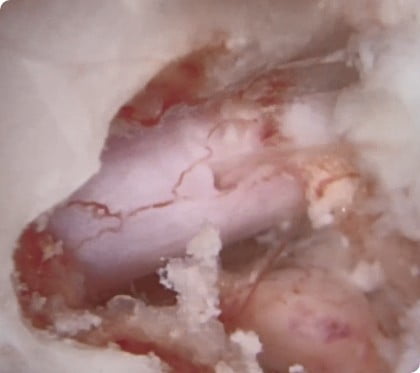

두 개의 작은 구멍을 통해 내시경과 수술 도구를 삽입해 정상 조직 손상은 최소화하고 돌출된 디스크만 제거하는 최소침습 척추 수술

기존 척추 수술은 절개가 크고 조직 손상이 많아 회복이 늦고 흉터·통증 부담이 크지만, 척추내시경 수술은 작은 절개로 병변만 정밀하게 제거해 조직 손상을 최소화

척추내시경을 통한 디스크수술

척추내시경수술 후 봉합범위